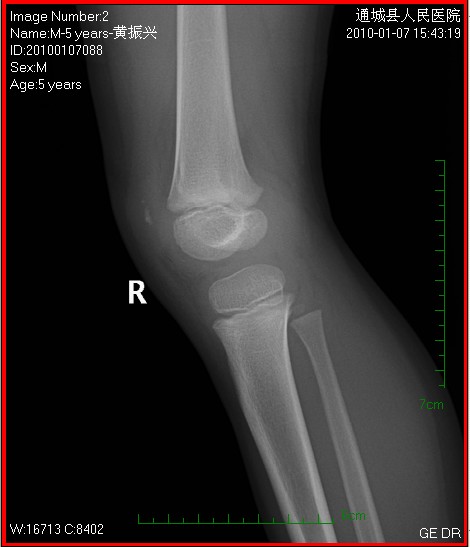

以下是引用随光逐影在2010-1-9 8:21:00的发言:[br]考虑左侧大、小腿外侧软组织内蔓状血管瘤伴左膝关节侵蚀,左侧髌骨及左侧股骨下端、胫骨上端骨骺异常发育。

以下是引用zxl51642在2010-1-9 17:29:00的发言:[br]首先要排除外敷药物等伪影,软组织血管瘤彩超没看见?[br]关节面凸凹不平,软骨及软骨下骨坏死,股骨内髁下方见碎骨片影,可能:1、首先考虑幼年型类风湿;2、股骨髁缺血性坏死,原因可能类似blount';s病机理;3、男性患儿查个尿排除尿黑酸症。